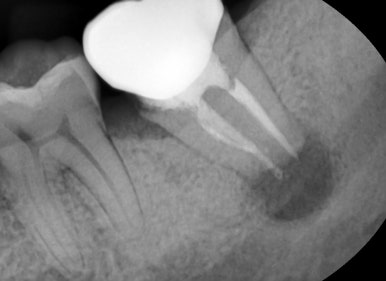

잇몸에혹으로 인해 내원해주신 환자분

치아 뿌리 끝 부분에 염증주머니가 생긴 것을 확인할 수 있습니다.

이런 치아 뿌리 끝 부분의 염증을 전문용어로 ‘치근단 농양’이라고 하는데요.

치아 뿌리 끝쪽에 염증이 생기는 경우는 충치가 심해지거나, 이전에 진행했던 신경치료가 충분하지 못했거나 하는

다양한 이유로 인해 신경이 괴사되면서 그 산물이 뿌리 끝에서 잇몸뼈쪽으로 나오는 경우인데요.

따라서 신경치료를 통해 신경을 완전히 제거해주고, 그 이후에 크라운을 씌워 수복해 치료를 해야합니다.